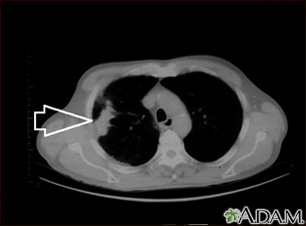

Lung mass, right lung - CT scan